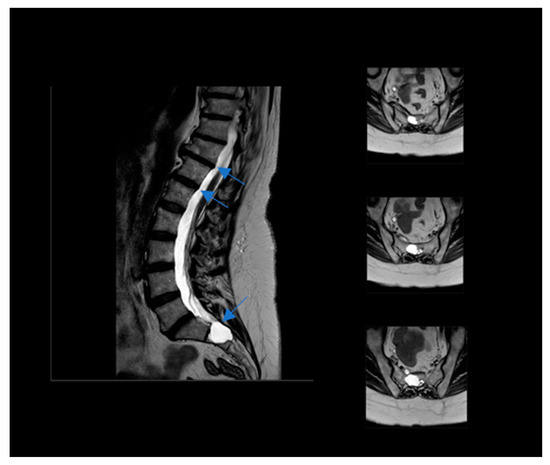

A 56-year-old woman was self-referred to us to start a ketogenic diet for the purpose of weight loss, but she also heard about a possible positive effect on pain related to the diet. At the first examination, her BMI was 35.6 (height 158 cm/weight 89.1 kg). She had an history of major depressive disorder, although it was not pharmacologically treated because of the low compliance to the treatments and the limited benefit she experienced by drugs. Moreover, she was affected by a severe dorsal in the tract between D8 and D11 and lower limb neuropathy due to the presence of multiple bilateral TCs localized in the tract between L4 and S2, with evidence of sacral bone erosive phenomena (see Figure 1). Neurological symptoms included: tingling, numbness, pins and needles, stabbing and shooting pain, stress incontinence, lack of coordination, sleep problems due to night-time pain, muscle weakness, difficulty in limb movements, and episodes of falling. A recent neurological examination evidenced antalgic posture, bilateral steppage gait, and reduced reflexes from the patellar down; Lasègue’s test was bilaterally positive at 45°. Upper motor signs, as clonus and Babinski sign, were absent. Under a therapeutic point of view, the patient was at the beginning addressed to physiotherapy, but with very limited benefits. Moreover, because of organizational issues, the patient was unable to follow treatments regularly, resulting in a low compliance to the treatments and the choice to stop them. In a neurosurgery consultation, she did not receive the indication to undergo the surgical procedure. Therefore, the only available treatment was a pharmacological one. Gabapentin up to 2400 mg/day and pregabalin up to 450 mg/day were ineffective on the symptoms. Duloxetine and amitriptyline were not tolerated by the patient. Additionally, different types of opioids gave her different side effects, inducing their discontinuation. The daily use of indomethacin lead to gastritis and she stopped the treatment. At the time of consultation, she regularly consumed 200 mg/day of celecoxib to reduce the pain, and, on demand, acetaminophen alone or in combination with codeine. Moreover, she was on the waiting list for a further neurosurgical consultation.

Figure 1.

Nuclear Magnetic Resonance of the patient Tarlov’s Cyst indicated by blue arrow.